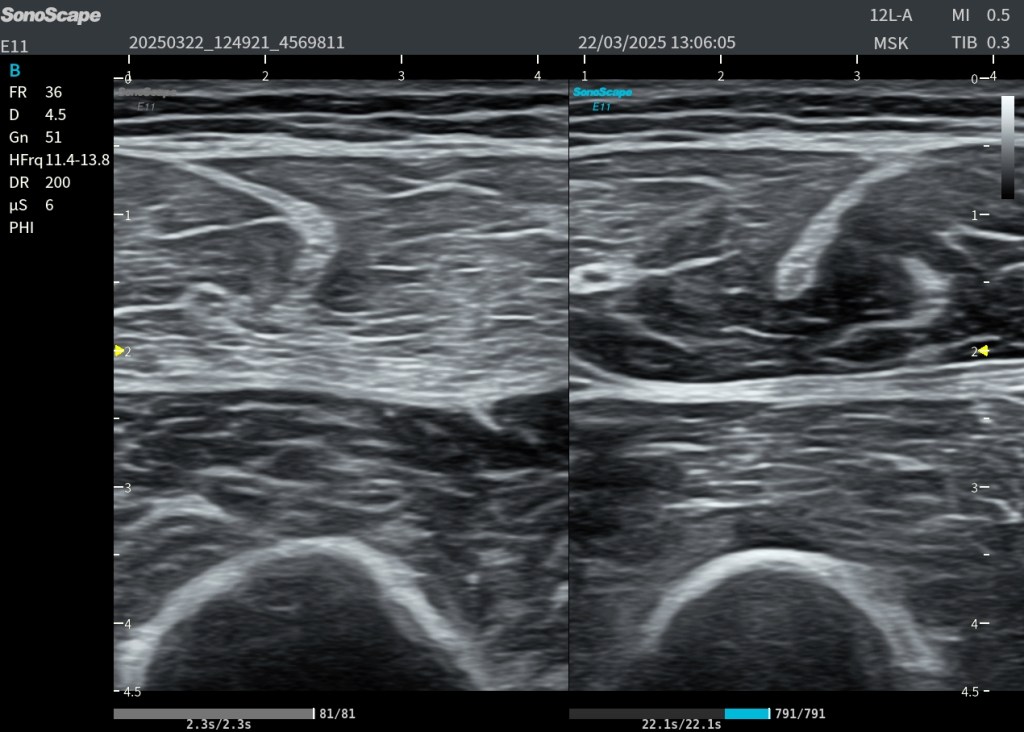

Para estudiarlo bien, no basta con verlo en un único corte. Es necesario explorarlo en transversal y en longitudinal.

El corte transversal permite reconocer el plexo entre los escalenos. El corte longitudinal ayuda a seguir las raíces y comprender su continuidad hacia los troncos. Esta maniobra es clave para no confundir el plexo con otras estructuras del cuello.